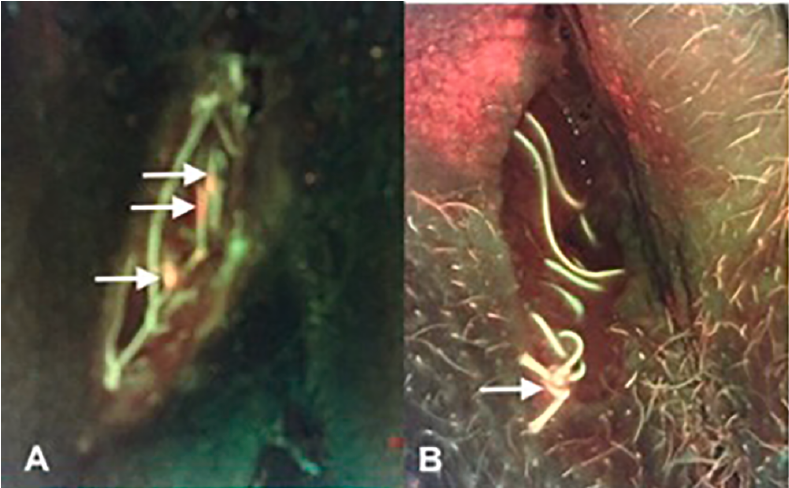

The “C-Swab” test: a technique for identifying bacteria in sinus tracts or tunneled wounds utilizing a cotton swab and bacterial fluorescence imaging

Andersen C. and McLeod K. Wounds 2025